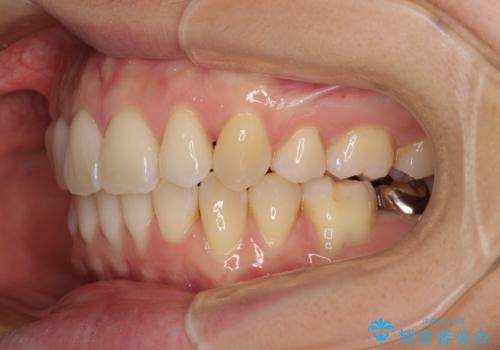

前歯のデコボコを抜歯矯正で改善 メタル装置で費用を抑える

もう少し口元の突出感を改善したかったのですが、舌の突出癖が影響し下顎前歯が唇側に押させる仕上がりとなりました。